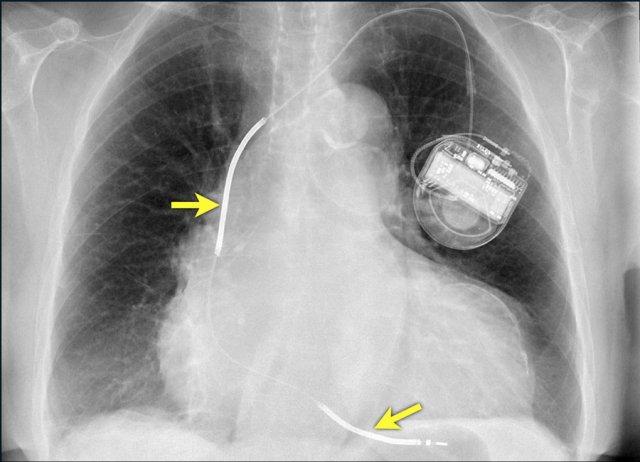

Các hình ảnh cho thấy máy tạo nhịp tim với điện cực nhĩ và điện cực thất.

Đầu điện cực nhĩ hướng lên trên và ra trước, vì vị trí lý tưởng là trong tiểu nhĩ phải, nơi điện cực được neo chặt vào các bè cơ thô.

Đầu điện cực thất được đặt tại mỏm thất phải, vị trí này nằm ở bên trái cột sống trên phim X-quang ngực thẳng và ở phía trước trên phim chụp nghiêng.

Hình ảnh được chụp ngay sau khi đặt ICD.

Có hình ảnh tràn khí màng phổi nhỏ (mũi tên).

Đây là biến chứng thường gặp nhất.